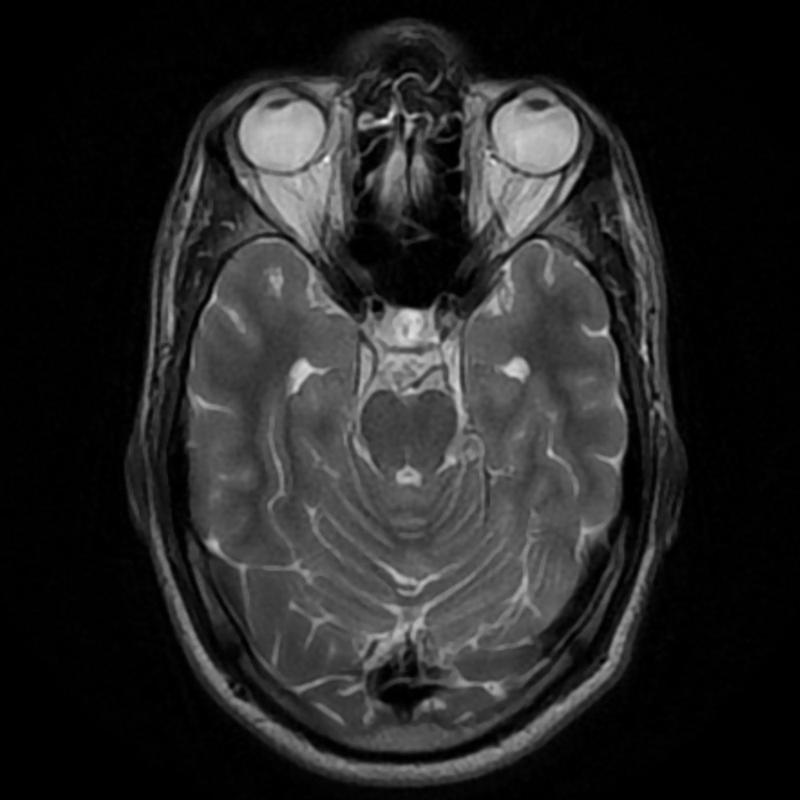

I just wanted to emphasize to people that sometimes the discontinuity between something like you would go to my eye doctor. I went to my ophthalmologist, and he was concerned that my visual field was dropping down over the years. One particular instance he said, "I want you to go have an MRI right now." We did and it showed up right away there was a meningioma, which is very a silent thing and a lot of people might have this. He said, "You got to get the emergency right away." It was like one of those--